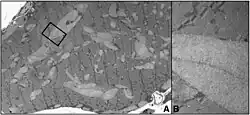

| A rendering of the human muscular form of phosphofructokinase. Mutations in the production of this enzyme are the cause of Tarui's disease.[3] The symmetry of the enzyme is a result of its tetrameric structure. | |